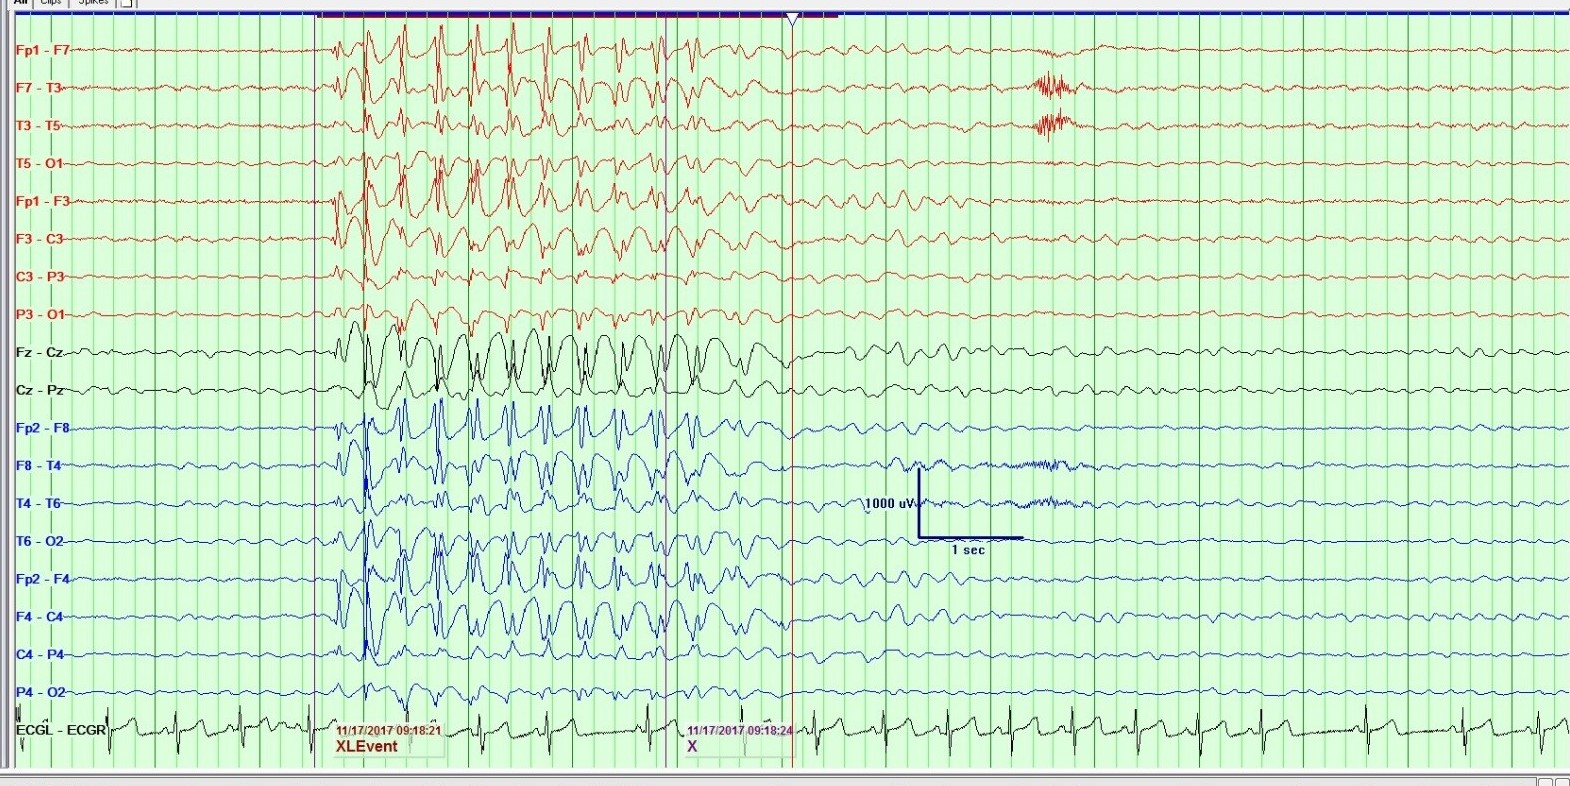

Lo que el electroencefalograma esconde. Reporte de caso.

Raquel Berzosa López, Roi Piñeiro Pérez

98-100